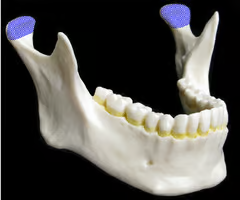

Mandibular condyle (forms TMJ)

Coronoid process

Mandibular notch

Ramus (“rami” = branches)

Mandibular angle (where ramus and body meet)

Body (forms the chin)

Mandibular foramen (nerves involved in tooth sensation - pass to lower jaw teeth - dentists inject Novocain to numb lower teeth)